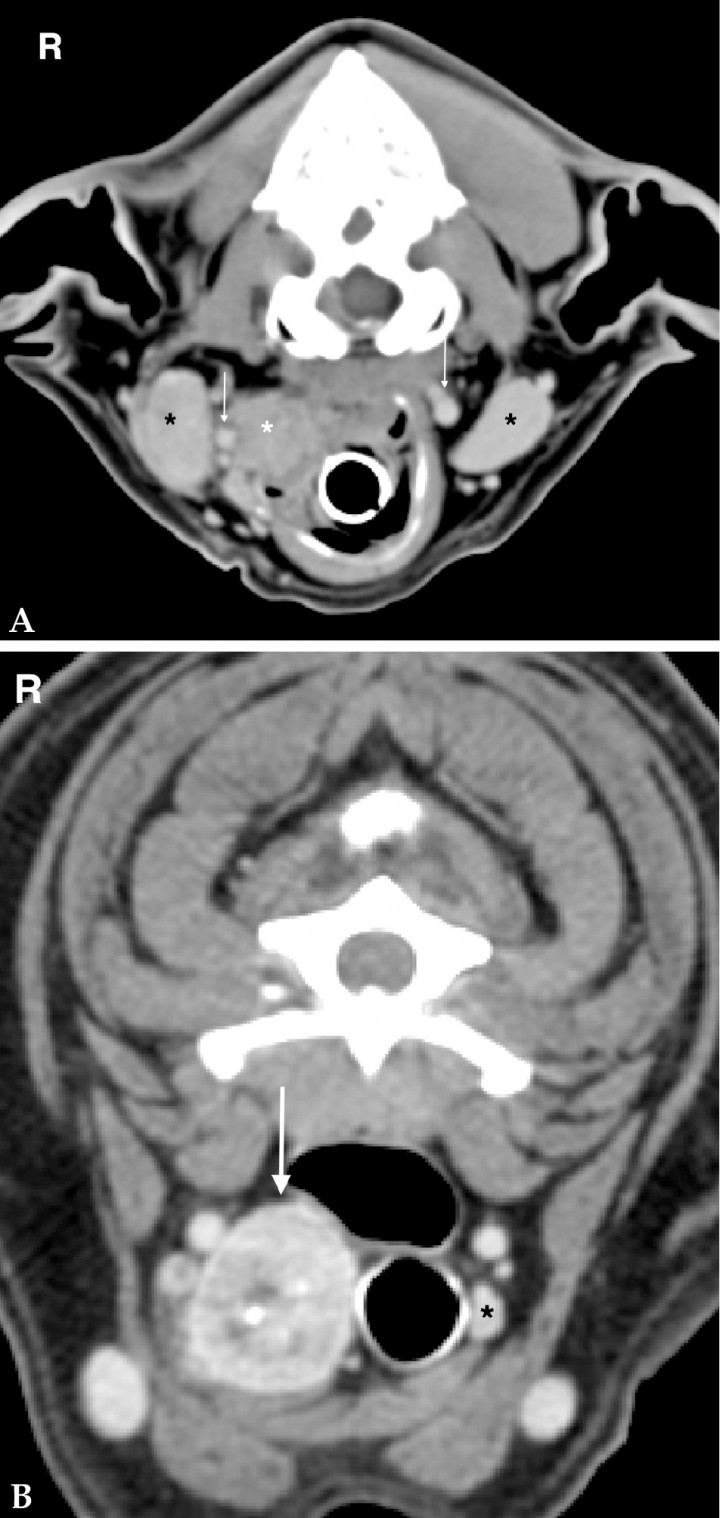

The role of CT in the staging process

The purpose of diagnostic staging is to assess the extension of local disease and to evaluate for regional and distant metastasis to evaluate treatment options.[ Biller B, Berg J, Garrett L et al.: 2016 AAHA Oncology Guidelines for Dogs and Cats. J Am Anim Hosp Assoc 2016; 52:181-204. [PubMed] ] To assess for regional metastasis, the corresponding sentinel lymph node (SLN), which is the first drainage area of a tumour, needs to be always included in the study and evaluated carefully. It has been suggested that the medial retropharyngeal lymph nodes, which are the sentinel lymph nodes for the head and cervical masses, are more likely to be metastatic than reactive if they present with an asymmetric size or a loss of a detectable hilus of the lymph node in CT; however cytologic or histopathologic examination remains vital (Fig. 10A).[ Nemanic S, Hollars K, Nelson NC et al.: Combination of computed tomographic imaging characterisitics of medial retropharyngeal lymph nodes and nasal passages aids discrimination between rhinitis and neoplasia in cats. Vet Radiol Ultrasound 2015; 56:617-627. [PubMed] ]

<p>(A) Transverse soft tissue window post contrast image of the neck of a 10 year-old Golden Retriever. The left mandibular lymph nodes are severely enlarged with indistinct margins and heterogeneous contrast enhancement (white arrow). Fine aspiration of the lymph node revealed metastasis of a squamous cell carcinoma of the nasal cavity. (B) Transverse lung window post contrast image of an 11 year-old Puggle with an oral melanoma. There are multiple, different sized, regularly marginated, soft tissue nodules throughout the whole lung parenchyma consistent with pulmonary metastasis (black arrows). R: right.</p>

Figura 10

(A) Transverse soft tissue window post contrast image of the neck of a 10 year-old Golden Retriever. The left mandibular lymph nodes are severely enlarged with indistinct margins and heterogeneous contrast enhancement (white arrow). Fine aspiration of the lymph node revealed metastasis of a squamous cell carcinoma of the nasal cavity. (B) Transverse lung window post contrast image of an 11 year-old Puggle with an oral melanoma. There are multiple, different sized, regularly marginated, soft tissue nodules throughout the whole lung parenchyma consistent with pulmonary metastasis (black arrows). R: right.

The lung is a common site of distant metastases among various neoplasms.[ Miles KG, Lattimer JC, Jergens AE et al.: A retrospective evaluation of the radiographic evidence of pulmonary metastatic disease on initial presentation in the dog. Vet Radiol Ultrasound 1990; 31:79-82. [Wiley] ] CT is the most sensitive modality for detection and assessment of pulmonary lesions in human and veterinary medicine.[ Choi DJ, Kwak JM, Kim J et al. Preoperative chest computerized tomography in patients with locally advanced mid or lower rectal cancer: Its role in staging and impact on treatment strategy. J Surg Oncol 2010; 102: 588-592. [PubMed] , Nemanic S, London CA, Wisner ER: Comparison of thoracic radiographs and single breath-hold helical CT for detection of pulmonary nodules in dogs with metastatic neoplasia. J Vet Intern Med 2006; 20:508-515. [PubMed] , Somboonporn C, Simthamnimit P, Puttharak W et al.: Role of chest radiography in the diagnosis and follow-up of pulmonary metastasis in differentiated thyroid cancer. J Med Assoc Thai 2010; 93 Suppl 3:S52-60. [PubMed] ] CT as a cross sectional modality and due to increased spatial resolution is superior to radiography in detecting pulmonary nodules (Fig. 10B). In conventional radiography, pulmonary nodules need to be at least 3 to 5 mm to be detected, whereas in CT pulmonary nodules of 1 mm are visualized. However, CT is not able to replace thoracic radiography for pulmonary metastasis monitoring, especially in light of recent concerns about cumulative diagnostic radiation dose from CT.[ Alexander K, Joly H, Blond L et al.: A Comparison of computed tomography, computed radiography, and film-screen radiography for the detection of canine pulmonary nodules. Vet Radiol Ultrasound 2012; 53:258-265. [PubMed] , Armbrust LJ, Biller DS, Bamford A et al.: Comparison of three-view thoracic radiography and computed tomography for detection of pulmonary nodules in dogs with neoplasia. J Am Vet Med Assoc 2012; 240:1088-1094. [PubMed] , Eberle N, Fork M, Von Babo V et al.: Comparison of examination of thoracic radiographs and thoracic computed tomography in dogs with appendicular osteosarcoma. Vet Comp Oncol 2010; 9:131-140. [PubMed] , Niesterok C, Köhler C, Ludewig E et al.: Comparison of projection radiography and computed tomography for the detection of pulmonary nodules in the dog and cat. Tierärztl Prax 2013; 41:155-162. [PubMed] ]